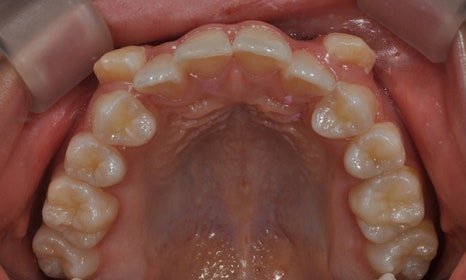

본 환자분은 오른쪽 아래 유구치(유치 어금니)가 남아있고 그 안쪽에 두번째 작은 어금니가 나와 있었습니다. 나머지 세 부위의 두번째 작은 어금니들은 영구치 치배가 없어 유치 어금니로 사용해온 상태였습니다. 왼쪽 아래는 뿌리만 남아있었고, 오른쪽 위에는 유치 어금니가 빠지고 공간이 비어 있었으며, 다행히 왼쪽 위 유치 어금니는 아직 남아 있는 상태였습니다. 아래는 오른쪽의 유치 어금니 및 왼쪽의 비어 있는 어금니 공간이 많이 남아 있고, 상대적으로 위에는 어금니 공간이 부족하여 위아래 앞니도 제대로 물리지 않고 있었습니다.

오른쪽 아래 치아들과 같이 치아가 겹쳐져 있게 되면, 교합이 맞지 않을 뿐만 아니라 그 사이 부위의 구강위생관리가 제대로 이루어질 수 없기 때문에 충치가 생길 확률이 높으며, 잇몸도 안좋아질 수 있습니다.